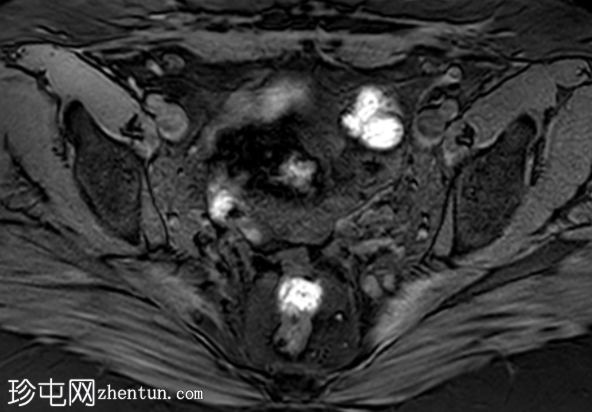

冠状位

T2加权像

盆腔MRI显示左侧骶前区有两个小囊性病变,位于左侧附件的预期解剖位置。

病变在T2加权像上呈高信号,边界清晰,囊壁轻度增厚,光滑。在T1加权脂肪抑制像上,一个病变内部呈高信号,另一个病变呈低信号。静脉注射对比剂后,可见轻度周边囊壁强化,未见强化的实性成分。

未见扩散受限。病灶与邻近盆腔血管关系密切,无周围炎症改变、盆腔淋巴结肿大或游离液体的证据。